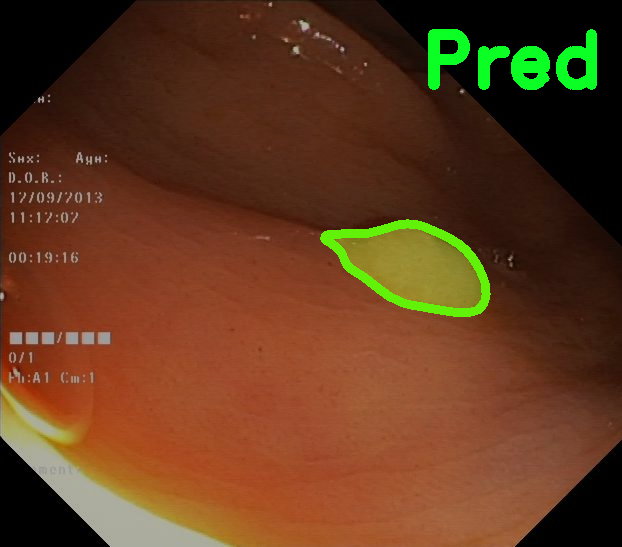

TransFuse is evaluated on both 2D and 3D datasets to demonstrate the effectiveness. As different medical image segmentation tasks serve different diagnosis or operative purposes, we follow the commonly used evaluation metrics for each of the segmentation tasks to quantitatively analyze the results. Selected visualization results of TransFuse-S are shown in Fig. 2.

Results of Polyp Segmentation. We first evaluate the performance of our proposed method on polyp segmentation against a variety of SOTA methods, in terms of mean Dice (mDice) and mean Intersection-Over-Union (mIoU). As in Tab. 3, our TransFuse-S/L outperform CNN-based SOTA methods by a large margin. Specifically, TransFuse-S achieves 5.2% average mDice improvement on the unseen datasets (ColonDB, EndoSene and ETIS). Comparing to other transformer-based methods, TransFuse-L* also shows superior learning ability on Kvasir and ClinicDB, observing an increase of 1.3% in mIoU compared to TransUnet. Besides, the efficiency in terms of the number of parameters as well as inference speed is evaluated on an RTX2080Ti with Xeon(R) Gold 5218 CPU. Comparing to prior CNN-based arts, TransFuse-S achieves the best performance while using only 26.3M parameters, about 20% reduction with respect to HarDNet-MSEG (33.3M) and PraNet (32.5M). Moreover, TransFuse-S is able to run at 98.7 FPS, much faster than HarDNet-MSEG (85.3 FPS) and PraNet (63.4 FPS), thanks to our proposed parallel-in-branch design. Similarly, TransFuse-L* not only achieves the best results compared to other Transformer-based methods, but also runs at 45.3 FPS, about 12% faster than TransUnet.